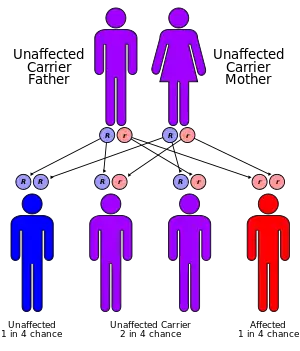

GSD I is inherited in an autosomal recessive manner. People with one copy of the faulty gene are carriers of the disease and have no symptoms. As with other autosomal recessive diseases, each child born to two carriers of the disease has a 25% chance of inheriting both copies of the faulty gene and manifesting the disease. Unaffected parents of a child with GSD I can be assumed to be carriers. Prenatal diagnosis has been made by fetal liver biopsy at 18–22 weeks of gestation, but no fetal treatment has been proposed. Prenatal diagnosis is possible with fetal DNA obtained by chorionic villus sampling when a fetus is known to be at risk.